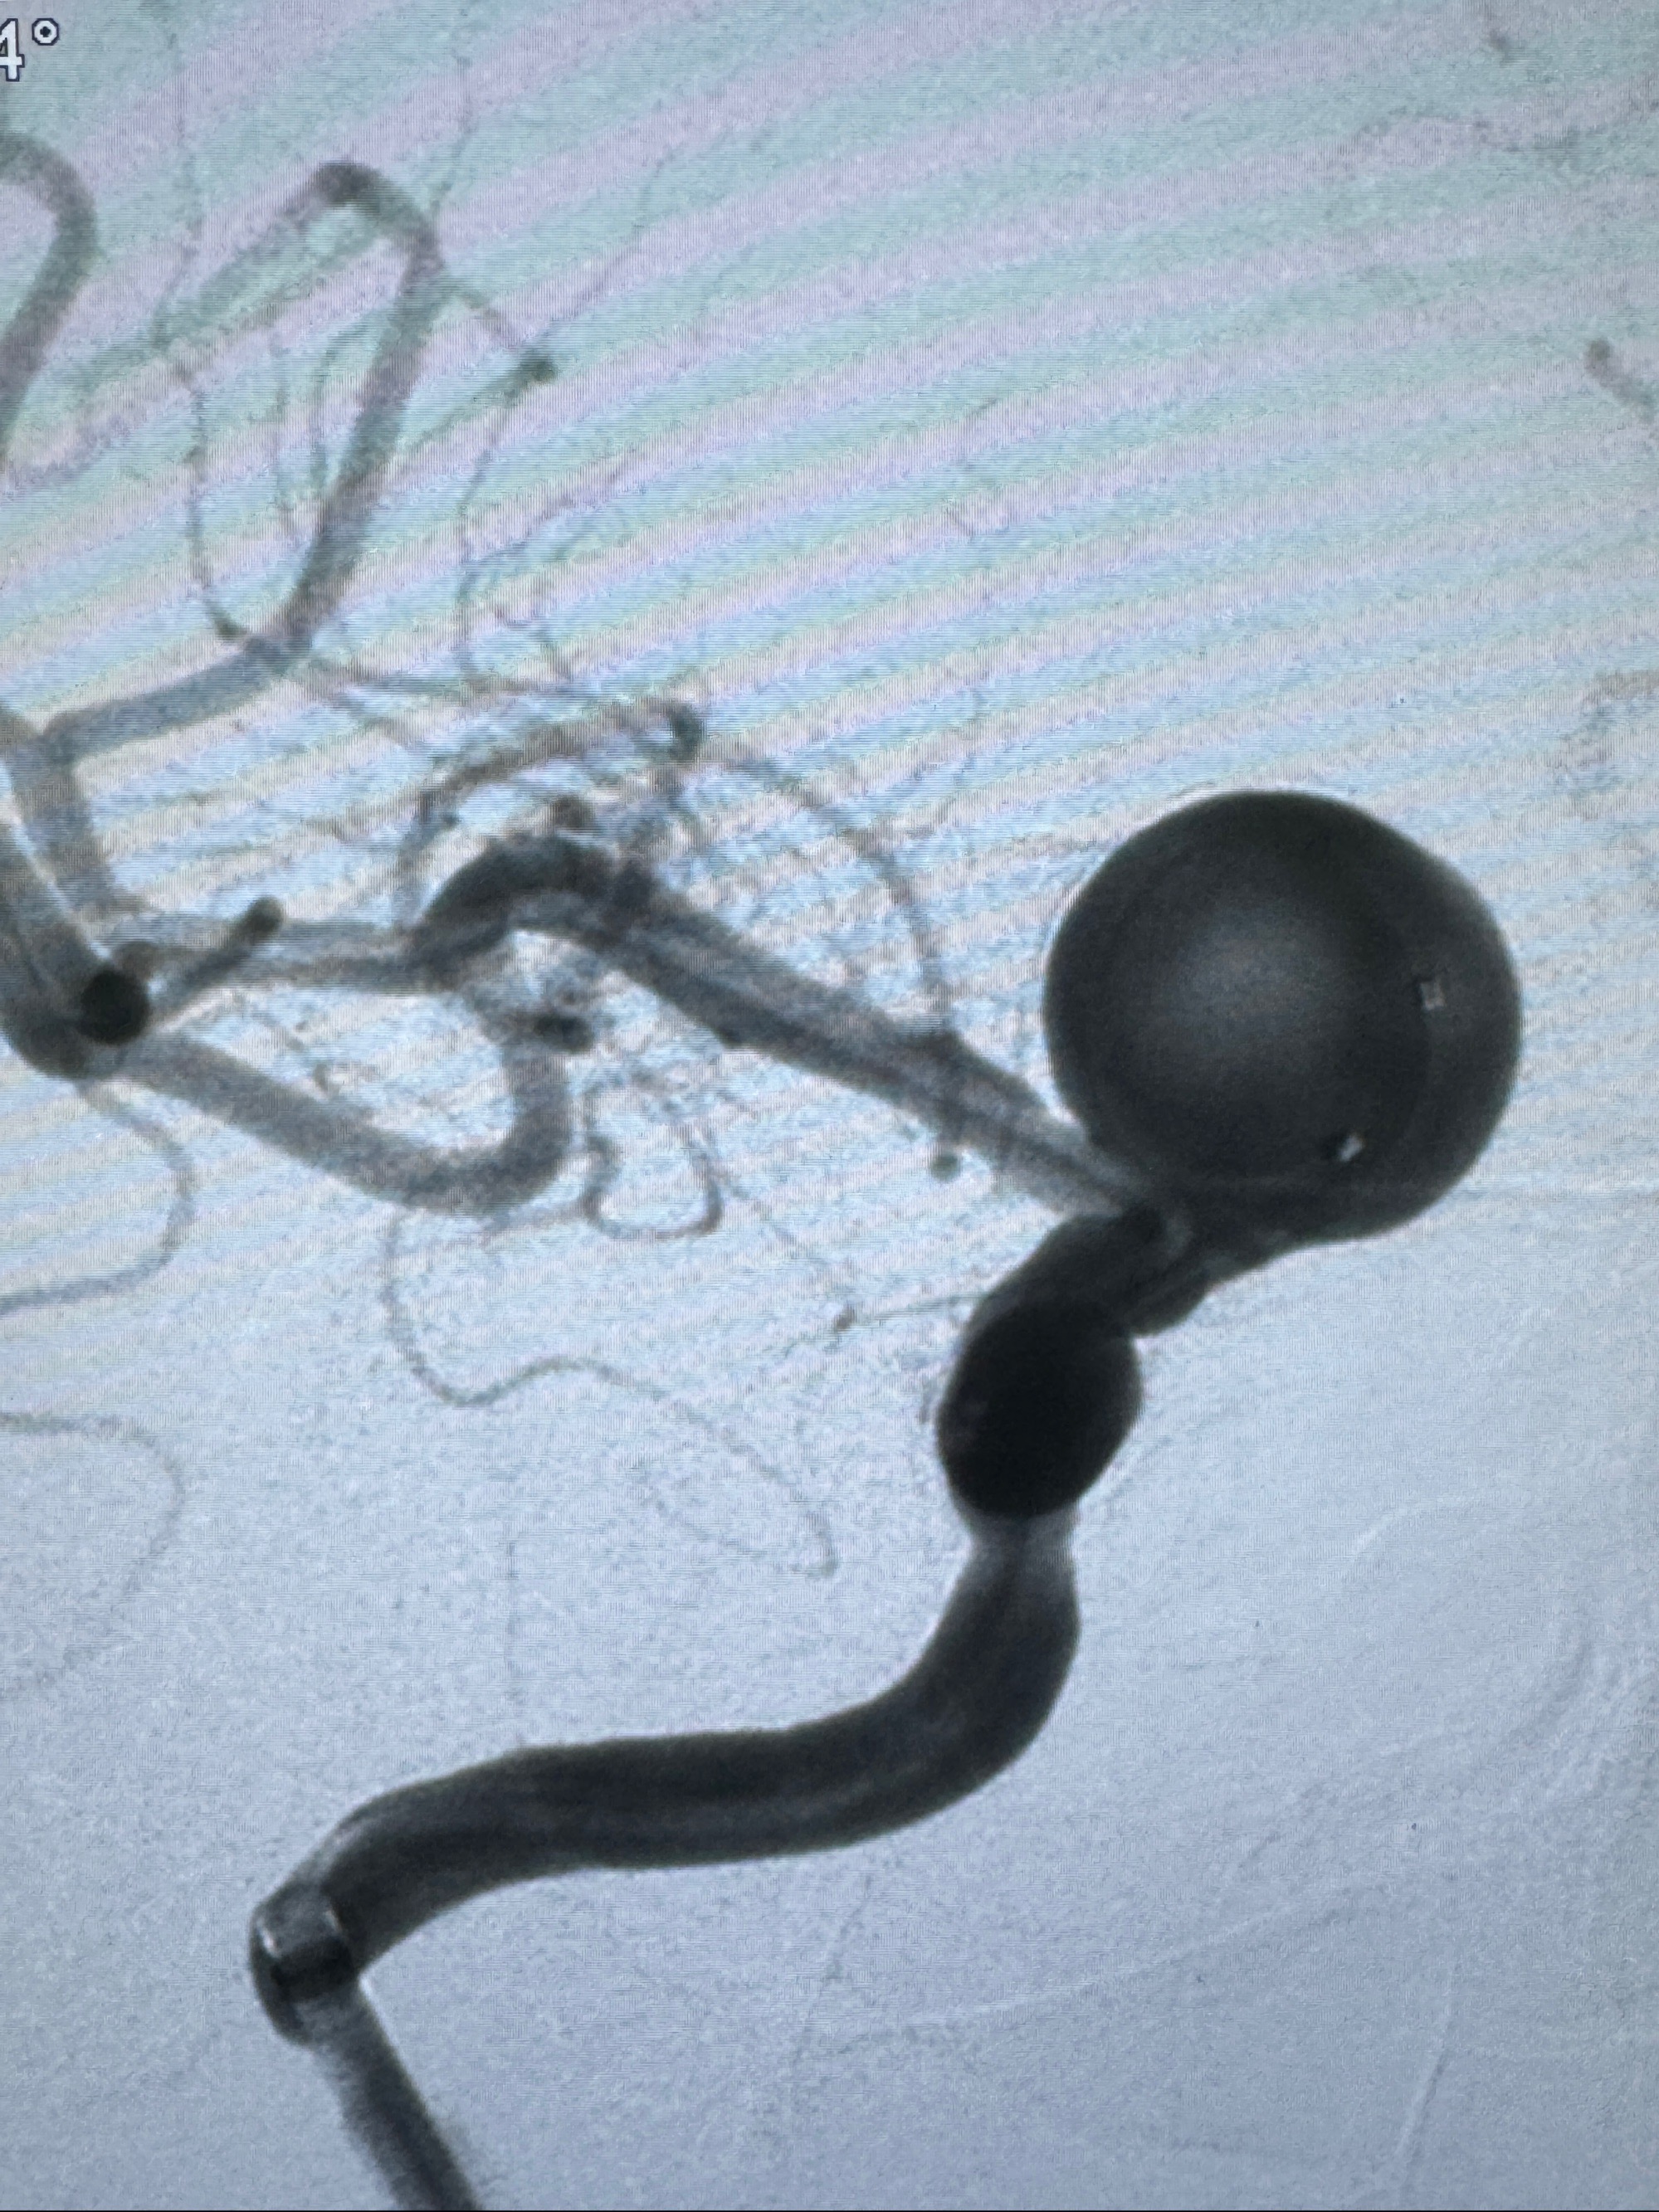

2023-12-08 复旦大学附属华山医院 全脑血管造影:右侧颈内动脉C6段动脉瘤,瘤颈6.68mm,动脉瘤大小13.28*12.34mm

2023-12-08外院DSA:右侧颈眼动脉瘤,约13*12mm大小,压颈试验显示左右向及后向前代偿可

测量动脉瘤的大小:16*13.8*7.6mm大小,较原先变大,考虑双抗后瘤内血栓溶解可能

观察动脉瘤腔内的血流动力学情况